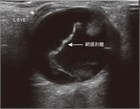

片頭痛の前兆は通常,原発性眼疾患に典型的な単眼ではなく両眼性の視覚変化を伴う.まれに後頭部の脳卒中が視覚変化を引き起こすことがあるが,これも一般に両眼性である.血管の危険因子や巨細胞性動脈炎の症状を伴う一過性の単眼性視力障害の患者では,一過性黒内障を考慮すべきである.網膜裂孔または網膜剝離はしばしば視覚障害を引き起こすが,一過性ではない.完全な網膜裂孔は通常,「影」または「暗幕」と表現される部分的な単眼視野欠損を呈する.網膜剝離は眼科医へ緊急紹介する必要があり,その見極めが重要である.硝子体出血は,単眼視力の喪失,視野の線状欠損,かすみ目等の症状が現れる.後部硝子体剝離,硝子体出血,網膜剝離は,ベッドサイドの超音波検査で確認できることがある.